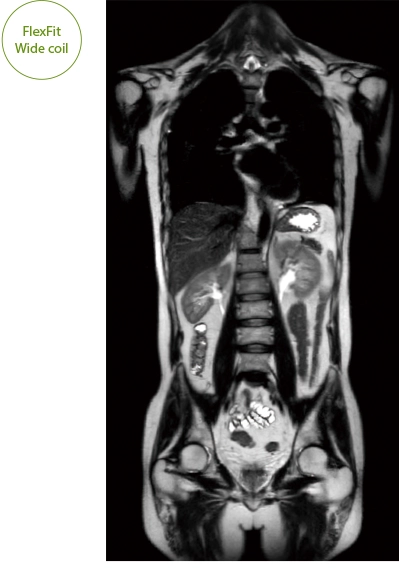

"DLR" is applicable to all body parts and promotes high speed imaging and diagnostic efficiency

IP-RAPID x DLR Plus can also shorten imaging time, allowing more images to be taken in the same examination time.

Additional imaging, such as different image types and cross sections, can be added to the conventional examination to increase the amount of information and make the diagnosis more reliable.

It can also be used with time-consuming scans such as Whole Body DWI and Whole Spine imaging, providing more detailed information in many areas than previously possible.